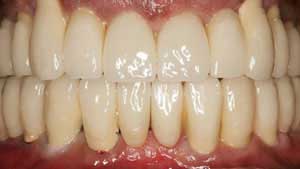

İmplant, sağlam, rahat ve güvenilir bir uygulamadır. İmplantlar üzerine yapılan protezler, gerçek dişlerin yerini alırken en doğal yapıyı oluştururlar. Eksik dişlerin tamamlanması sürecinde, sağlıklı dişlere dokunulmamış olur. Sağlam dişlerimizin protez yapmak amacıyla kesilmemesi elbette çok önemli bir avantajdır.Ayrıca implantlar diğer protez seçeneklerine oranla çok daha uzun ömürlüdür.

İmplant üzerine yapılan diş, doğal dişiniz gibi görünür, doğal performans gösterir.